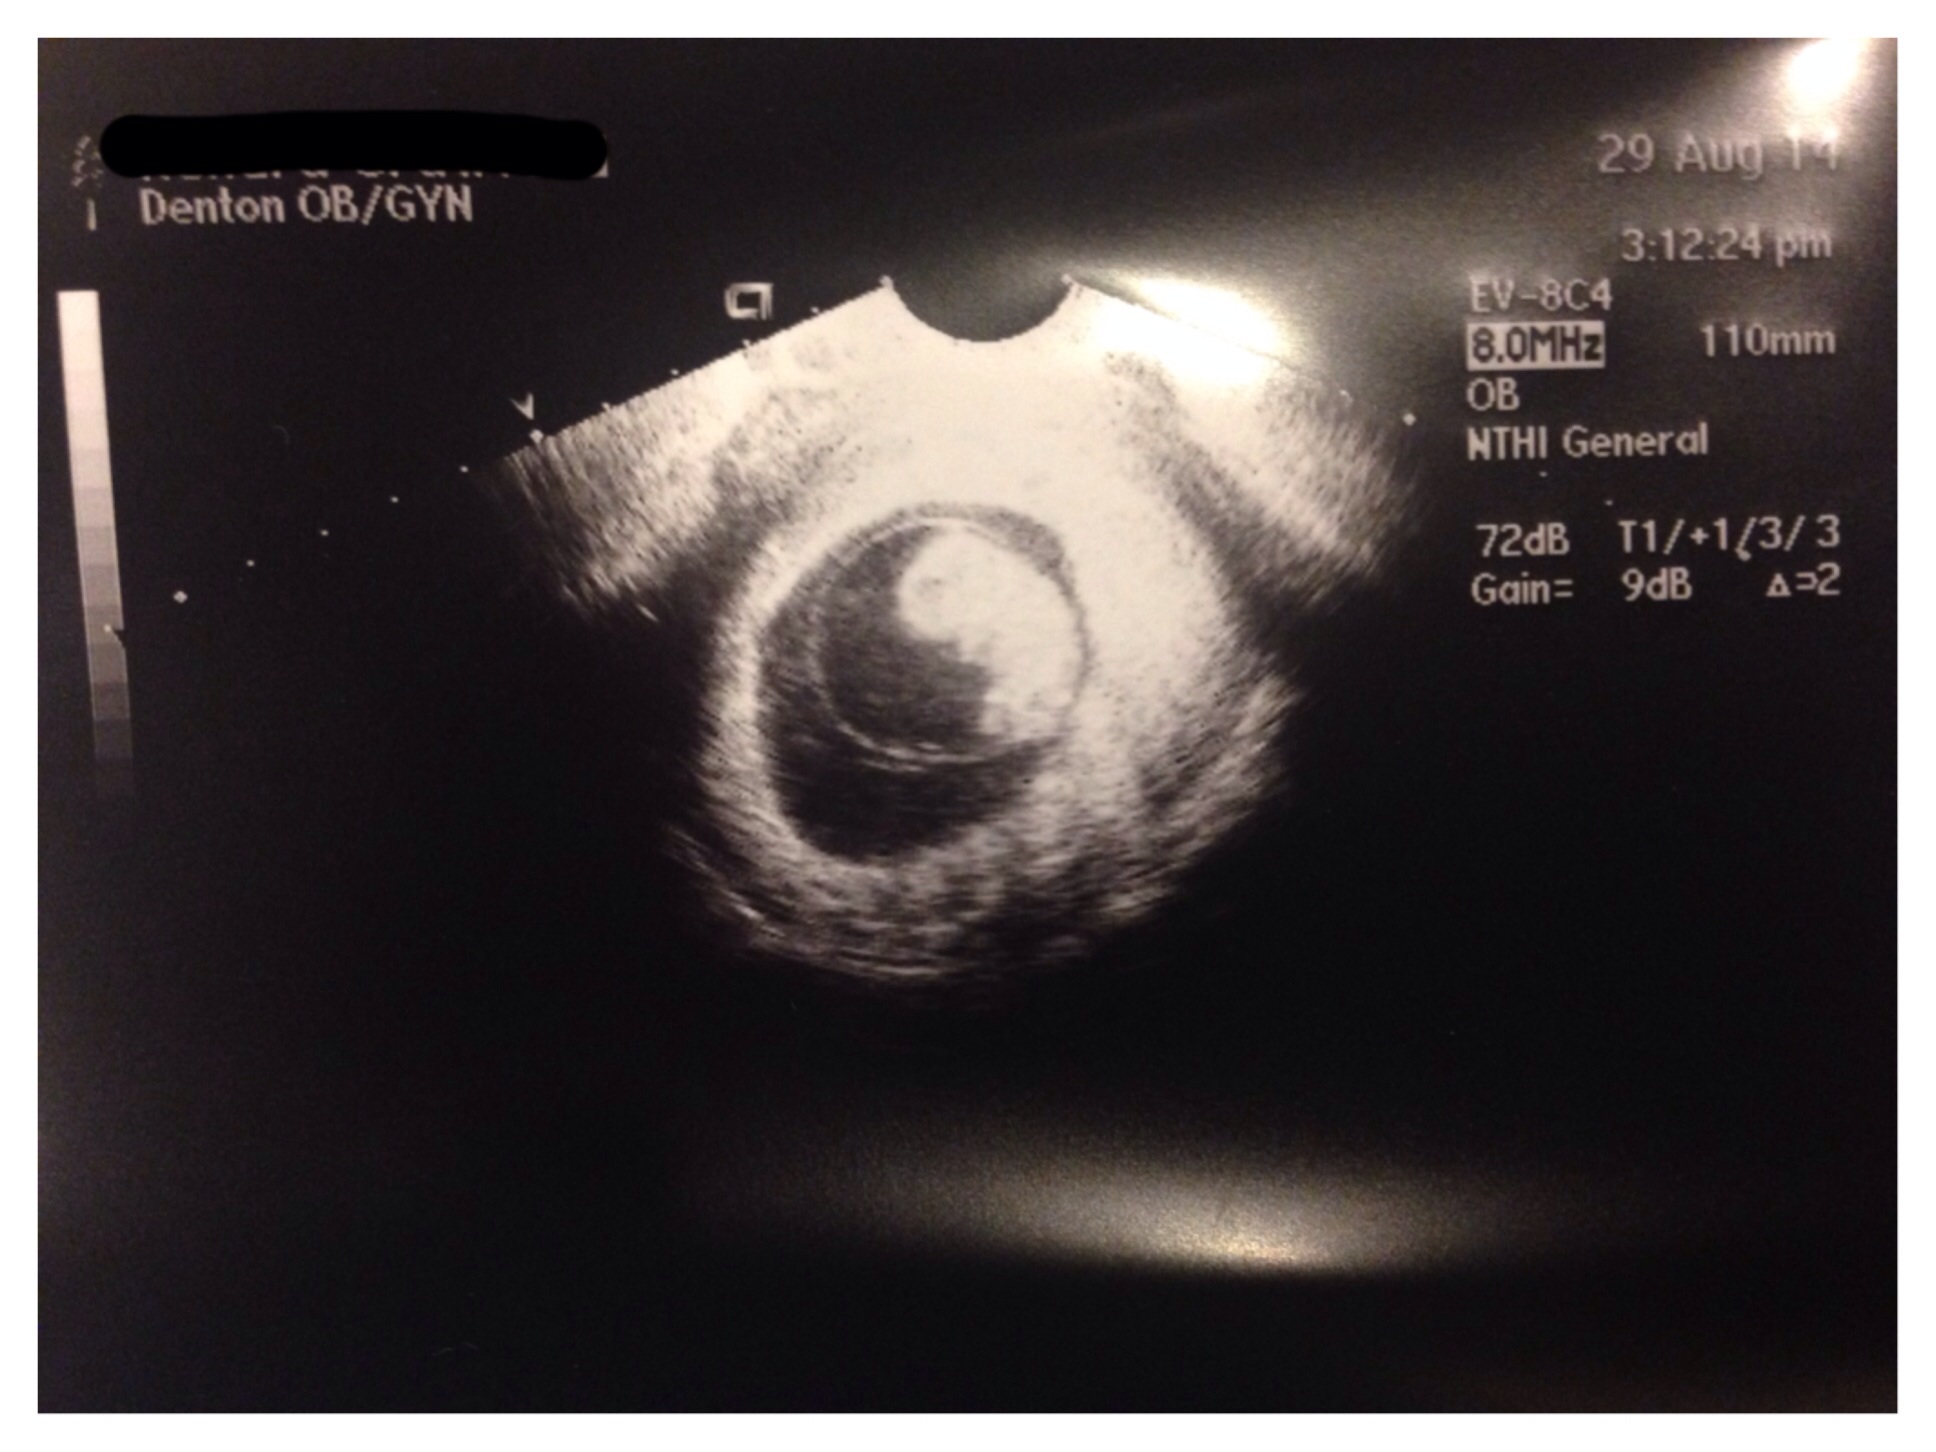

I've been lurking for about 3 weeks, so here's my intro. I'm a twenty-something newlywed with a 10 year old daughter from north Texas. My husband and I were married in May and are now expecting a surprise around March 29th 2015. He is not my daughter's father, this will be his first. I lost 2 pregnancies in my previous relationship. We are cautiously optimistic and haven't told anyone other than immediate family as of yet. I am primarily mobile, so I apologize for the lack of avatar/siggy. I promise to figure that out soon. Meanwhile, here is a picture from our appointment on Friday at 9weeks 5 days. Looking forward to "meeting" everyone!